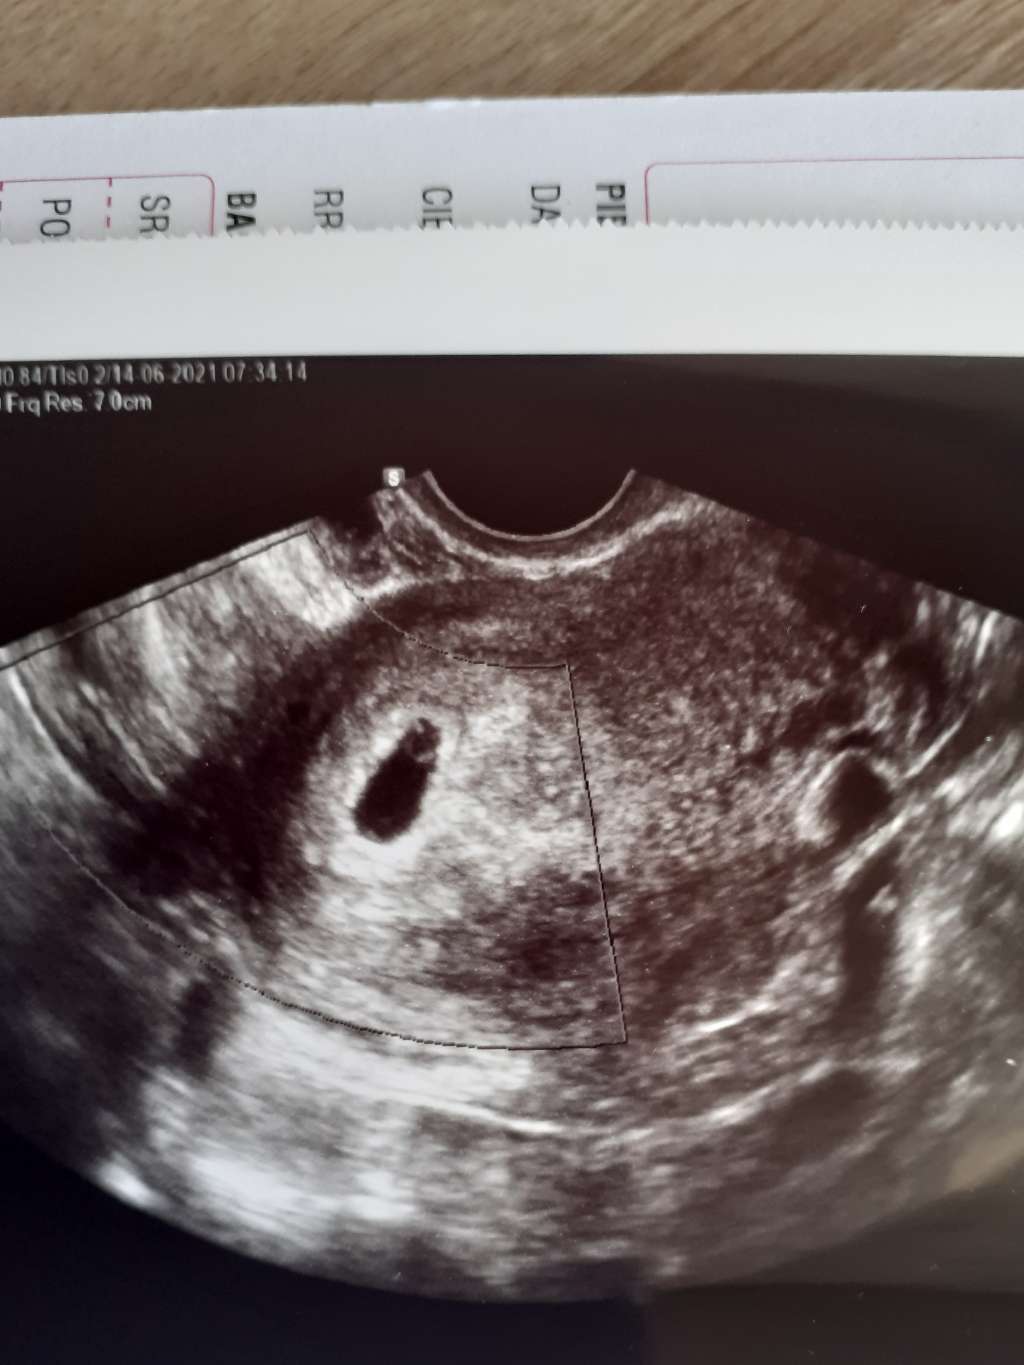

a zacznę od tego że wczoraj zaczęłam plamić dość obficie na taki beżowy kolor i od razu czarne myśli nerwy...ale jakoś się ogarnęłam i myślę sobie co ma być to będzie jakoś wytrzymie do dzisiejszej wizyty i na wizycie USG dopochwowe nic nie widać ja już serce w gardle ale gin mówi że może przez zrosty po CC słabiej widać (w tym gabinecie USG bardzo leciwe) i stwierdził sprawdzimy przez brzuch a tu kuźwa DWIE!!! Małe kuleczki

ale że słaby sprzęt to za tydzień mam przyjechać do innego gabinetu mojego gin i tam zobaczymy dokładniej co i jak. Na razie nie chce się cieszyć zabardzo bo z tymi początkami ciąży a zwłaszcza w bliźniaczych odpukac różnie bywa. A do tego luteina pod język 3razy dziennie i jakieś globulki na tą infekcje co mnie dopadła o której ostatnio pisałam.i na razie tyle u mnie za tydzień będę mieć lepszy obraz sytuacji.